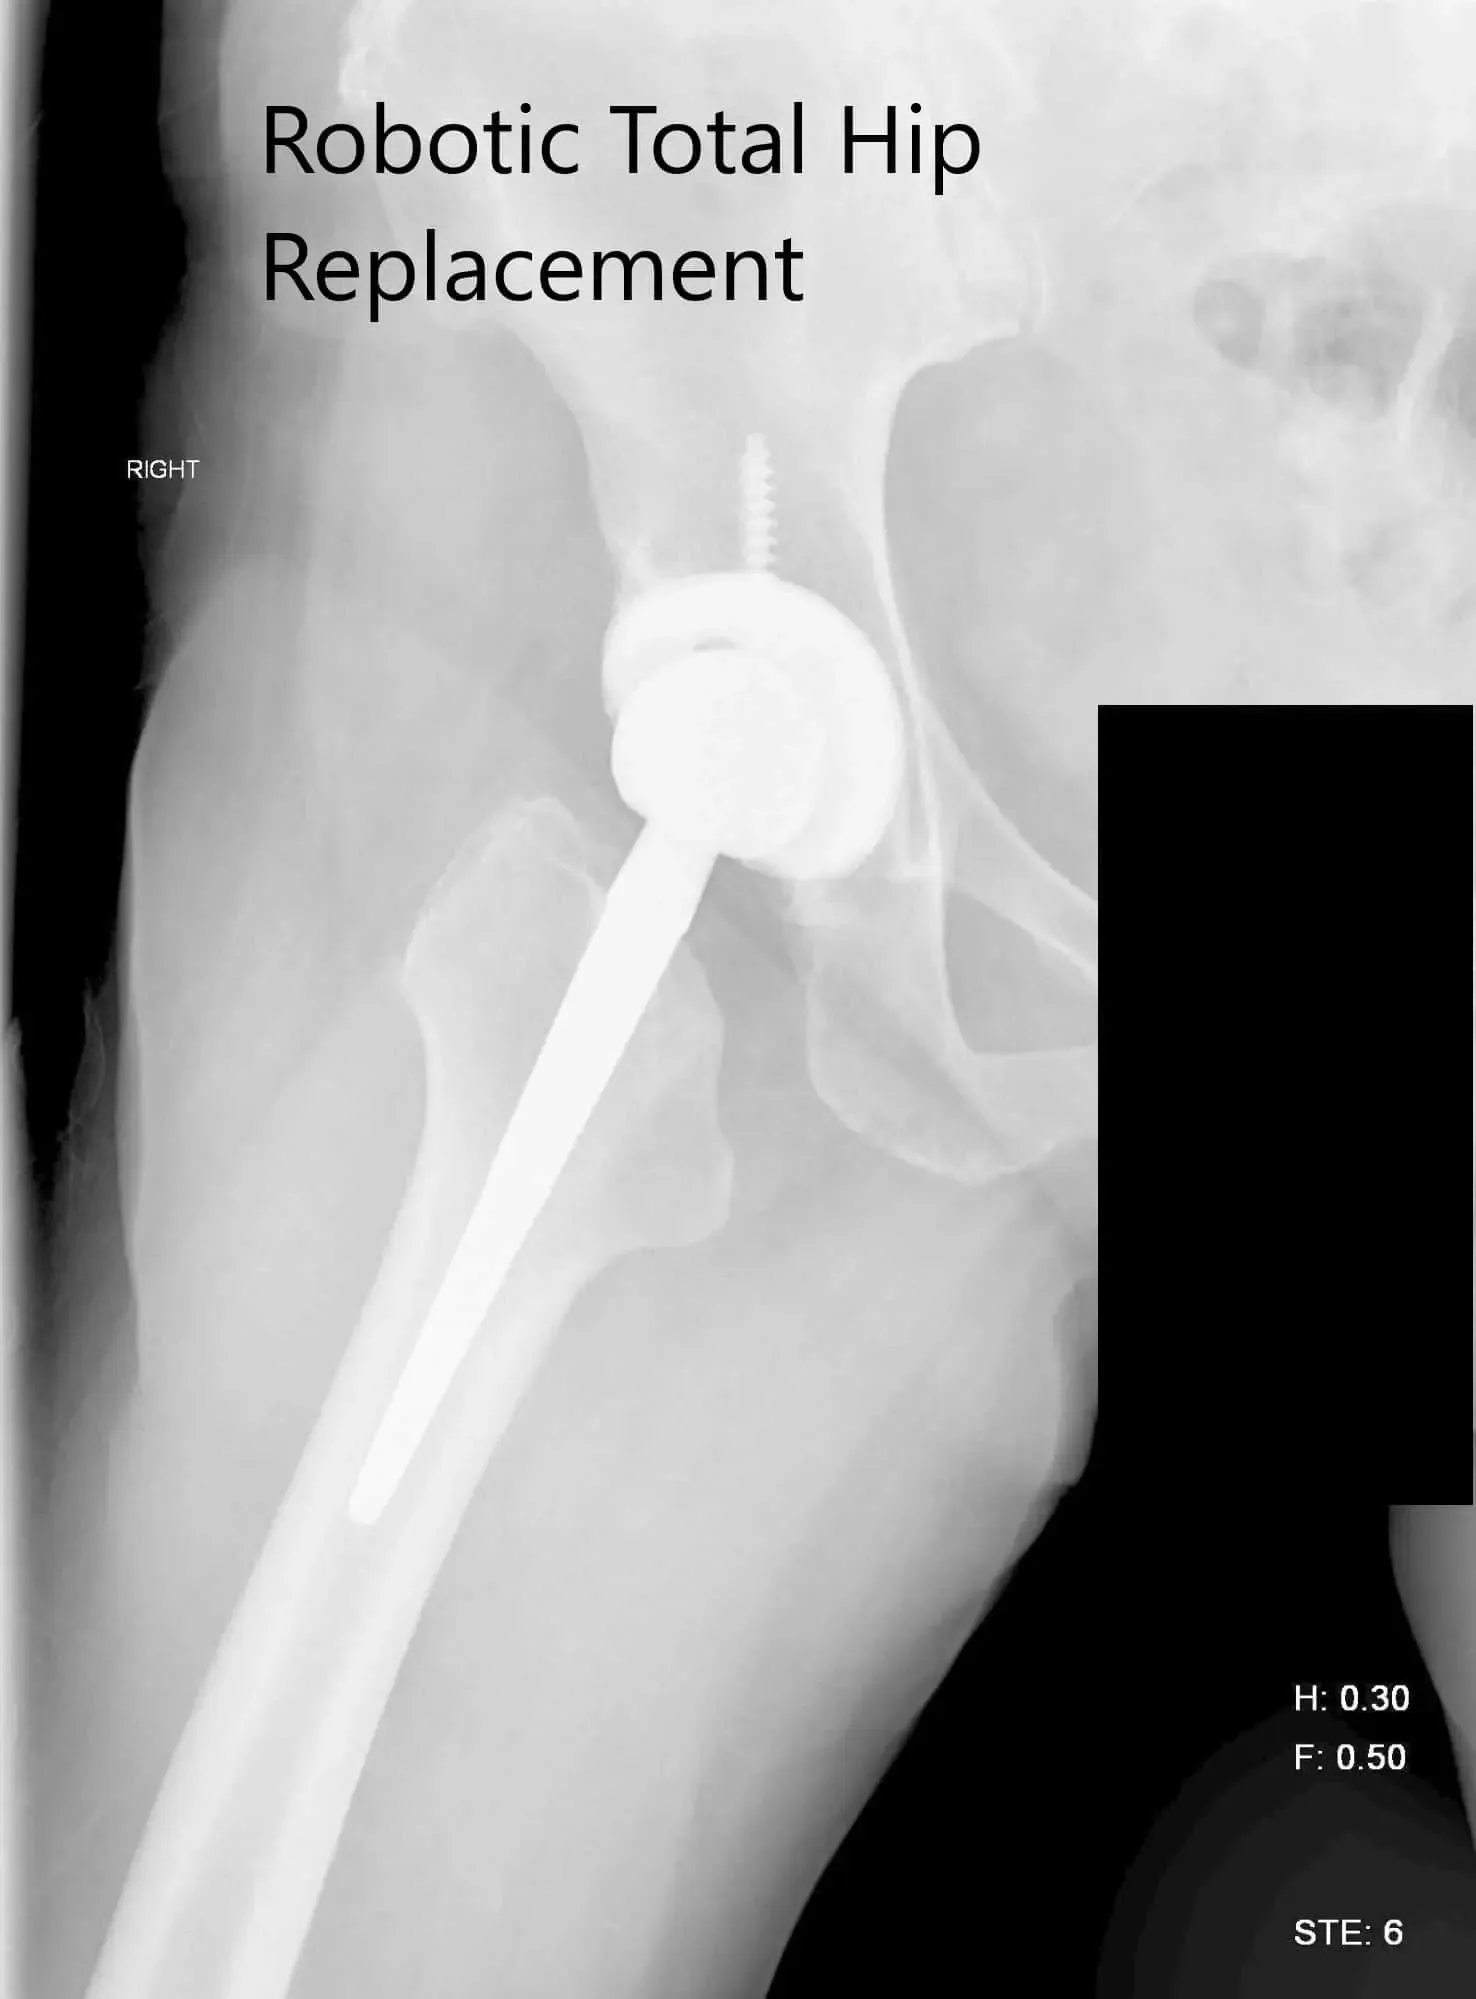

Postoperative X-ray of the right hip showing AP and lateral view.

IMPLANTS USED: Tritanium cluster shell 52-mm with 6.5-mm x 30-mm screw with a Trident shell. Zero degrees poly with a 127-degree stem with a ceramic head, outer diameter 32-mm minus 4.